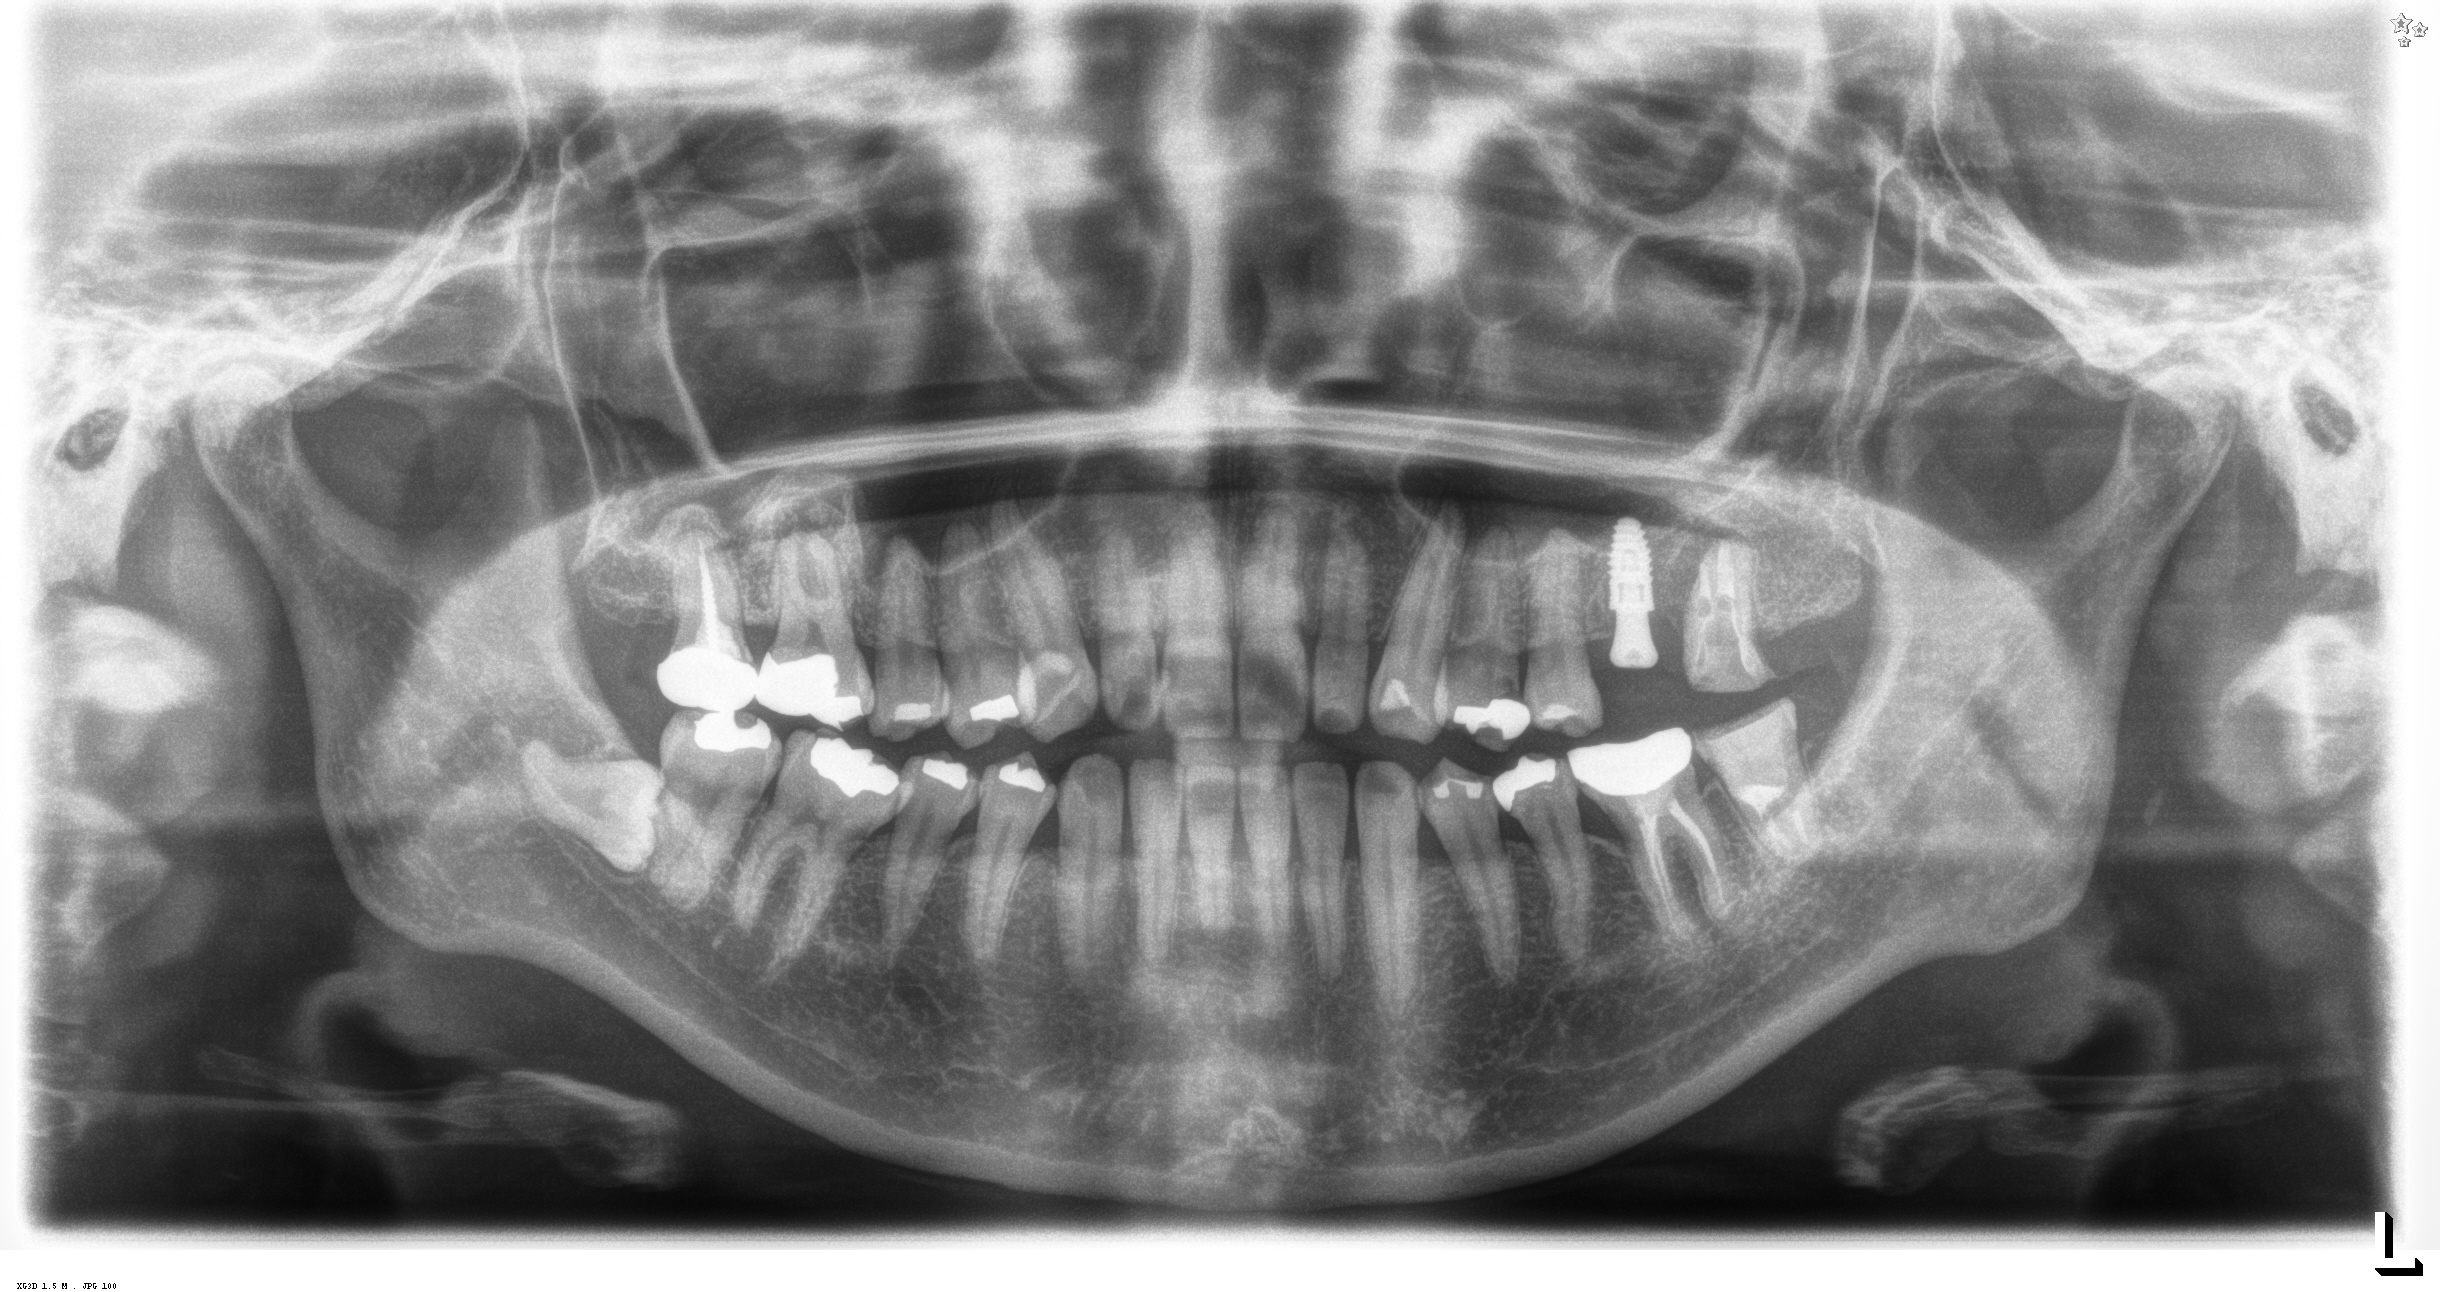

今日午前中のソケットリフトを併用したOPEも

ガイドを使用し

ハッチを開け

フルガイドで埋入

ほらメスも糸も使わない1回法。次回は型取り

右上の時間を見て頂ければ分かりますが

13分で終わっています。